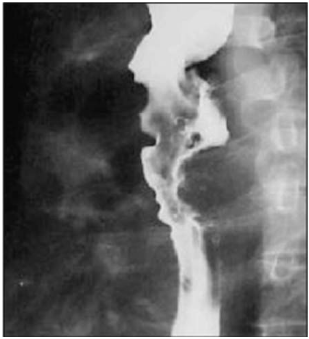

Disponível em: <www.scielo.br>. Acesso em: 16 fev. 2023.

Um paciente de 71 anos de idade apresentou queixa de disfagia cervical, associada a deglutição ruidosa, regurgitação, abaulamento cervical esquerdo, acessos de tosse, halitose e emagrecimento progressivo há três anos. Ele, então, procurou o cirurgião de cabeça e pescoço para investigar essa sintomatologia, o qual optou pela realização de exames de imagem, que evidenciaram as imagens apresentadas.

Qual é a hipótese diagnóstica mais plausível?